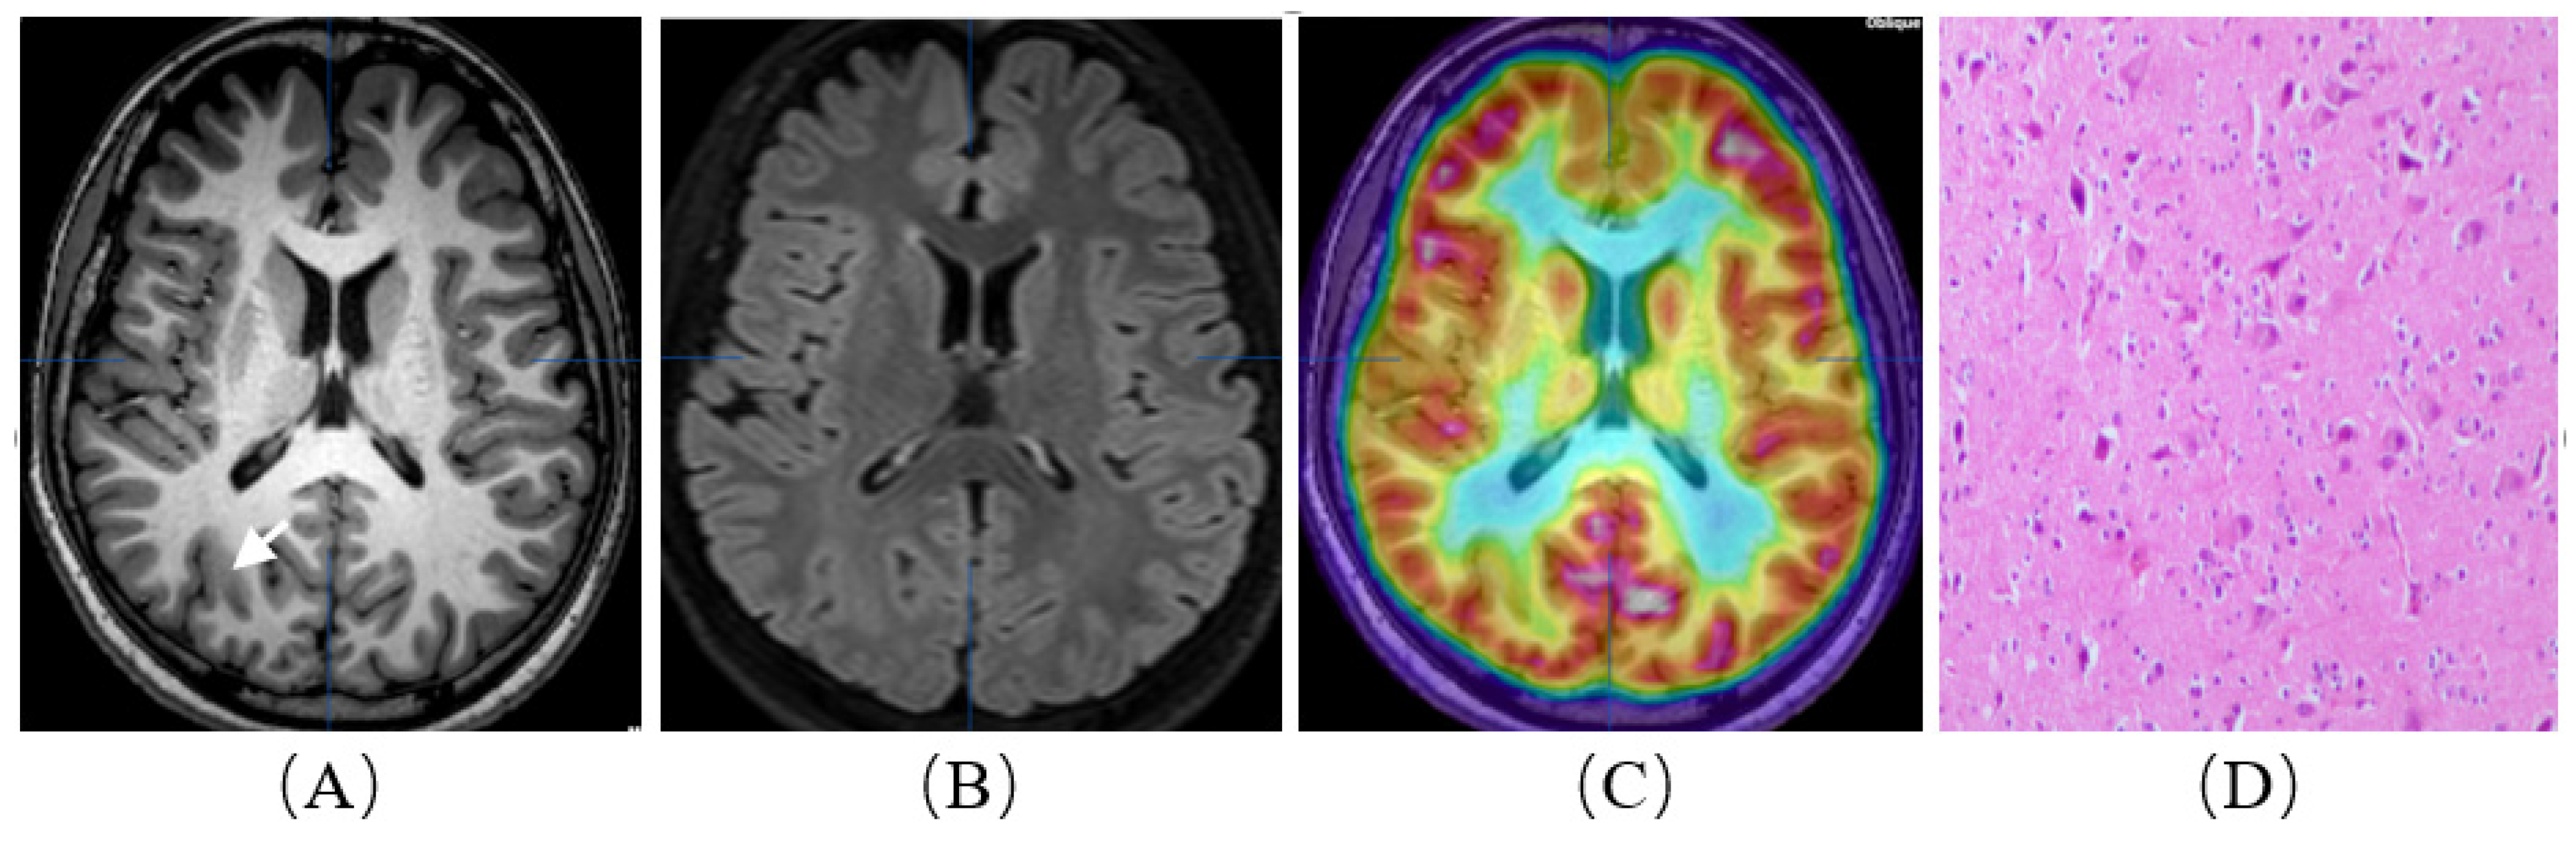

Figure 2.

A patient with refractory epilepsy to drug therapy. He was born in 2003 and was admitted when he was 14 years old. His first seizure occurred at two years old. Interictal and ictal EEG recordings indicated the right parietal occipital lobe region. MRI showed cortical and subcortical signal abnormalities on axial TIWI (A) and FLAIR T2WI (B) in the right parietal occipital lobe. (18F)-FDG PET/MRI images (C) demonstrated hypometabolism in the parietal occipital lobe extending also to the parietal occipital area on the right. Resective surgery was planned for the patient, and an intracranial electrode was not used. Postoperative histopathological examination (D) confirmed ‘type II a, focal cortical dysplasia’. The patient is currently seizure-free (Engel I).